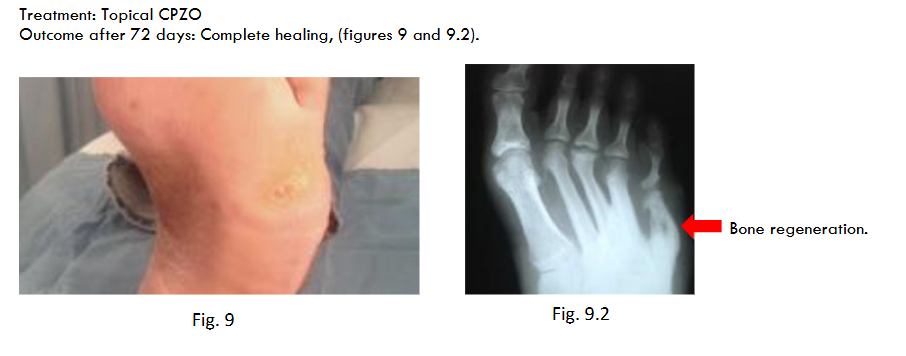

Treatment: Topical CPZO

Outcome after 72 days: Complete healing.